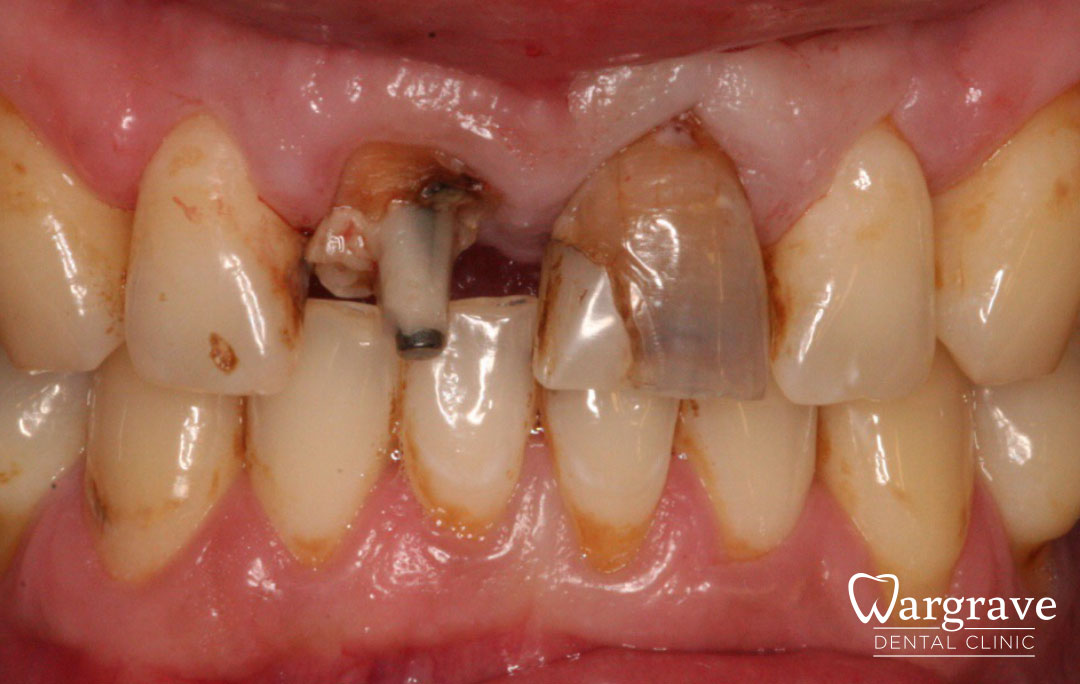

Healthy Smiles These are more advanced examples of different treatments available.All cases shown were carried out by Dr R Khurana unless otherwise stated. Immediate implants Anterior Mandible Bone Regeneration Anterior Mandibular Implant Bridge Maxillary Anterior Implant Bridge Implant stabilised ‘Life Like’ replacement dentures Implant Bridge after 10-years with zero bone loss Implant examples including ZBLC concepts Adhesive Bridge solution for a missing premolar Multidisciplinary care Orthodontics, Replacement veneers and composite bonding Adhesive Bridge solution for missing central incisors Replacement crown, Veneer and Composite Bonding Replacement Crowns and Veneer Injection Moulding using Composite Resin Equilibration Tooth Whitening to treat Developmental Discolouration